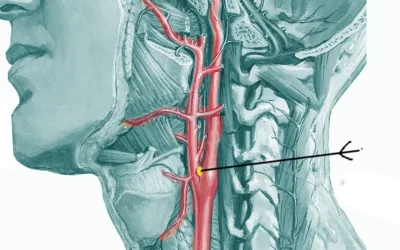

اهمیت درمان تومور کاروتید زمانی مشخص میشود که همه چیز را درباره این تومور عروقی بدانید. تومور کاروتید یا پاراگانگلیوما...

تومور پاروتید

تومور پاروتید یک رشد غیرعادی سلولی در غده پاروتید است که بزرگترین غده بزاقی بدن محسوب میشود و در جلوی گوش و در ناحیه فک...